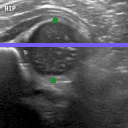

The correlation statistics are already high enough for our automated tool to be widely adopted for infant hip screening. It is nevertheless essential to acknowledge that the false negative cases are not to be taken lightly. In Fig. 5 we illustrate the subtle differences between individual scans from the four possible categories. Fig. 5(a) shows a true positive example, with AFHC=39.6%, an error of less than 0.04% to SGT. It is worth noting that, for 128×128128128128{\times}128 pixel images, a disagreement of one pixel represents a percentage difference of 0.78% across the whole image, and approximately 1.5% across the span of the femoral head structure. Fig. 5(b) shows a true negative example, with AFHC=62.4%, an error of less than 0.39% to SGT. Fig. 5(c) shows the most severe of the false positives. The algorithm under-segments the lowermost component of the femoral head, with AFHC=43.3%, compared to a SGT FHC of 50.4%. Fig. 5(d) shows the most severe of the false negatives. The algorithm over segments the lowermost component of the femoral head and also slightly over segments the ilium on its upper edge by including a small bump of cartilage. There is only little of the horizontal length of the ilium visible in the image; this affects the ilium edge disproportionately, and thus the algorithm calculates AFHC=60.1%, whereas the SGT FHC is 49.9% (a figure which would have caused a clinician to keep the patient under observation).

Refer to caption

(c)

Fig. 5: Qualitative analysis of AFHC% and its corresponding diagnostic outcomes: (a) True positive. (b) True negative. (c) False positive. (d) False negative diagnosis.